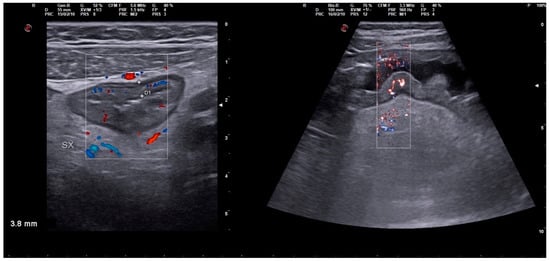

Severe Typhoid Fever Complicated by Superior Mesenteric and Splenic Vein Thrombosis

2. Case Description